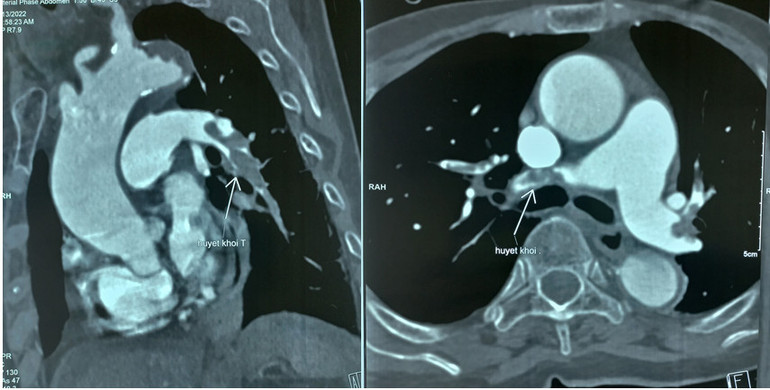

Bệnh nhân N.T.T. (92 tuổi), vào viện vì gãy xương đùi phải có chỉ định thay khớp háng. Trong quá trình phẫu thuật đột ngột tụt huyết áp, nhịp tim chậm dần, các bác sĩ nhanh chóng nghĩ ngay đến hiện tượng thuyên tắc động mạch phổi và chụp CT động mạch phổi.

Hậu Covid-19, bệnh lý thuyên tắc động mạnh phổi có chiều hướng gia tăng -0

Bệnh nhân N.T.T. 92 tuổi sốc tim do thuyên tắc động mạch phổi cấp hai bên.

Bệnh nhân được dùng thuốc tiêu sợi huyết cấp cứu ngay trên bàn phẫu thuật, kết hợp hồi sức tim mạch tích cực trước, trong và sau mổ. Tình trạng của bà sau khi được chẩn đoán và điều trị kịp thời tiến triển tốt lên theo từng giờ. Hiện tại bà đã tỉnh táo và có thể tự sinh hoạt bình thường.